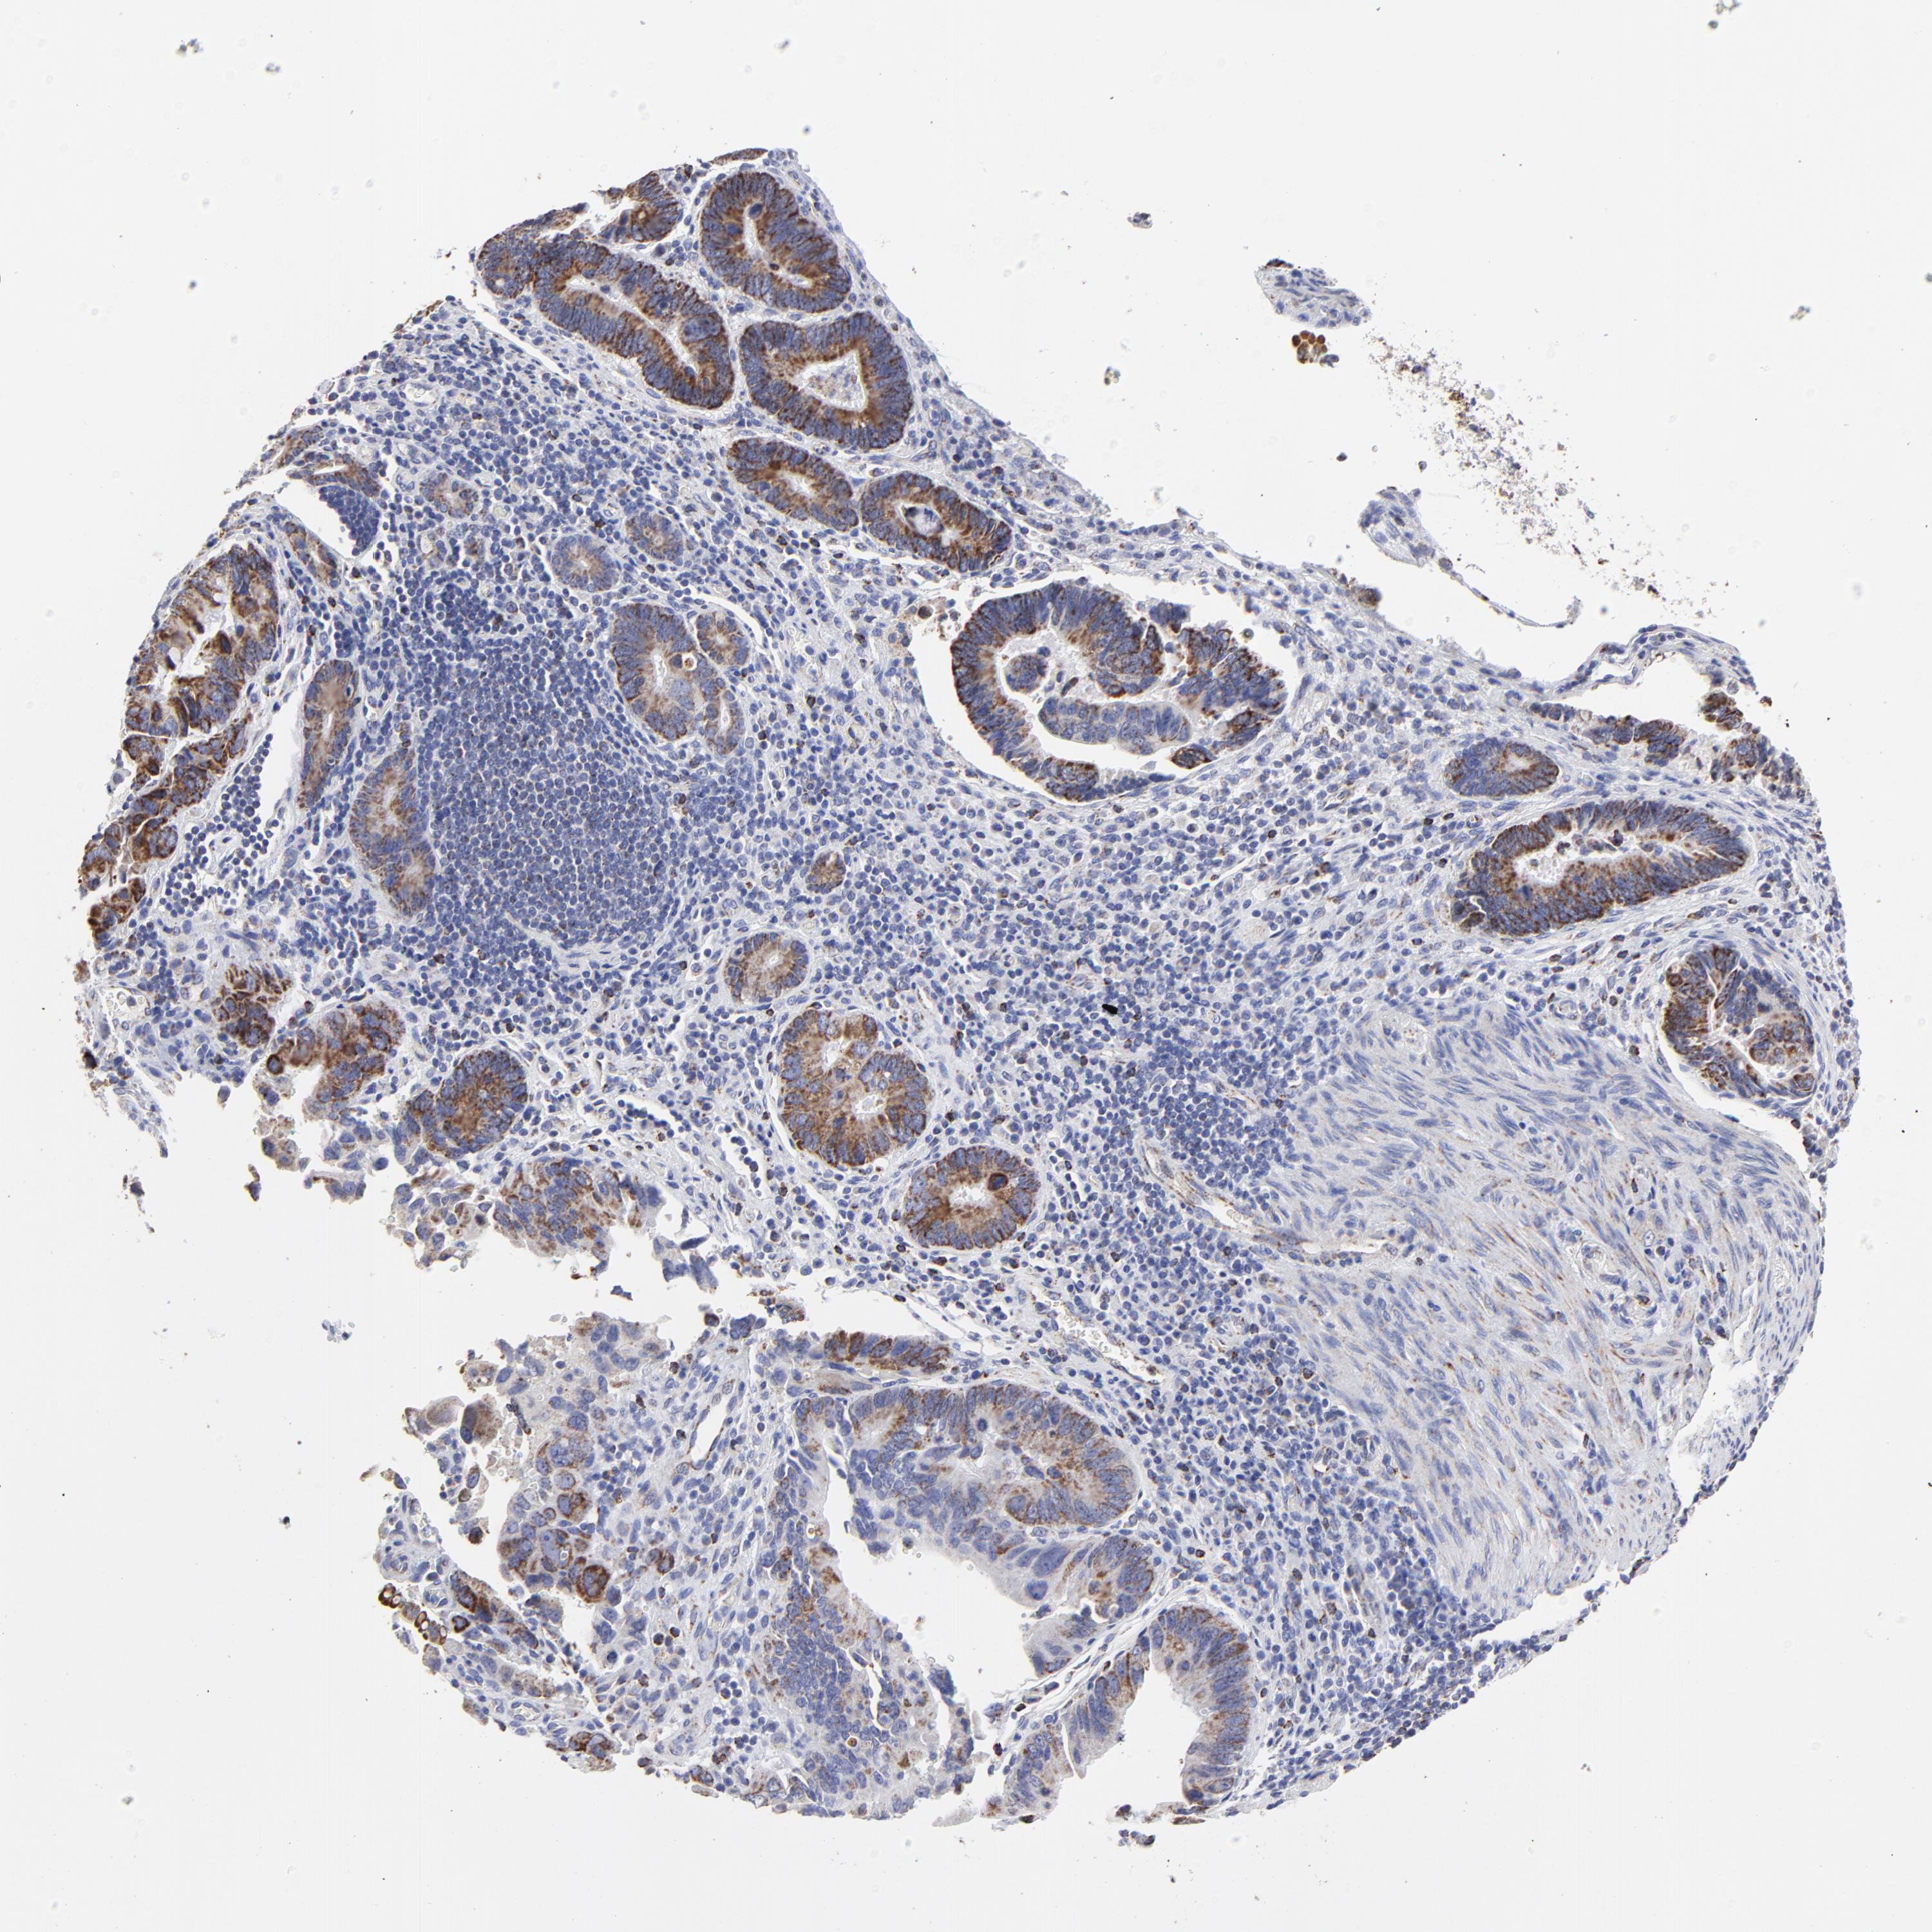

PANCREATIC CANCER - Protein expressioni

A mouse-over function shows sample information and annotation data. Click on an image to view it in a full screen mode. Samples can be filtered based on level of antibody staining by selecting one or several of the following categories: high, medium, low and not detected. The assay and annotation is described here.

Note that samples used for immunohistochemistry by the Human Protein Atlas do not correspond to samples in the TCGA dataset.

Antibody stainingi

Antibody staining in the annotated cell types in the current human tissue is reported as not detected, low, medium, or high, based on conventional immunohistochemistry profiling in selected tissues. This score is based on the combination of the staining intensity and fraction of stained cells.

Each image is clickable and will lead to virtual microscopy that enables deeper exploration of all samples and also displays staining intensity scores, fraction scores and subcellular localization as well as patient and tissue information for each sample.

Antibody HPA001931

Antibody CAB026191

Staining

High

Medium

Low

Not detected

Intensity

Strong

Moderate

Weak

Negative

Quantity

>75%

75%-25%

<25%

None

Location

Nuclear

Cytoplasmic/membranous

Cytoplasmic/membranous,nuclear

Adenocarcinoma, NOS